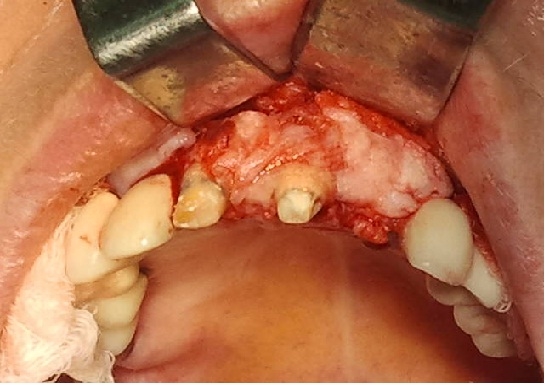

Bogata w płytki i leukocyty fibryna jest stosowana w regeneracji tkanek od ponad 15 lat. Pozytywny wpływ PRF (platelet-rich fibrin) na regenerację tkanek miękkich jest niewątpliwy, bezsporny i częściowo udowodniony w badaniach klinicznych i analizach biochemicznych. Wpływ PRF na regenerację tkanki kostnej jest obserwowany klinicznie, ale nadal niedostatecznie poznany jest mechanizm tego zjawiska.

Platelet- and leukocyte-rich-fibrin has been used in regeneration of tissue for more than 15 years. The positive influence of PRF on the regeneration of soft tissue is undoubtedly, without question and partially proven in clinical studies and biochemical analysis. Influence of PRF on regeneration of bone tissue is observed clinically but the mechanism of this phenomenon is still not sufficiently known.